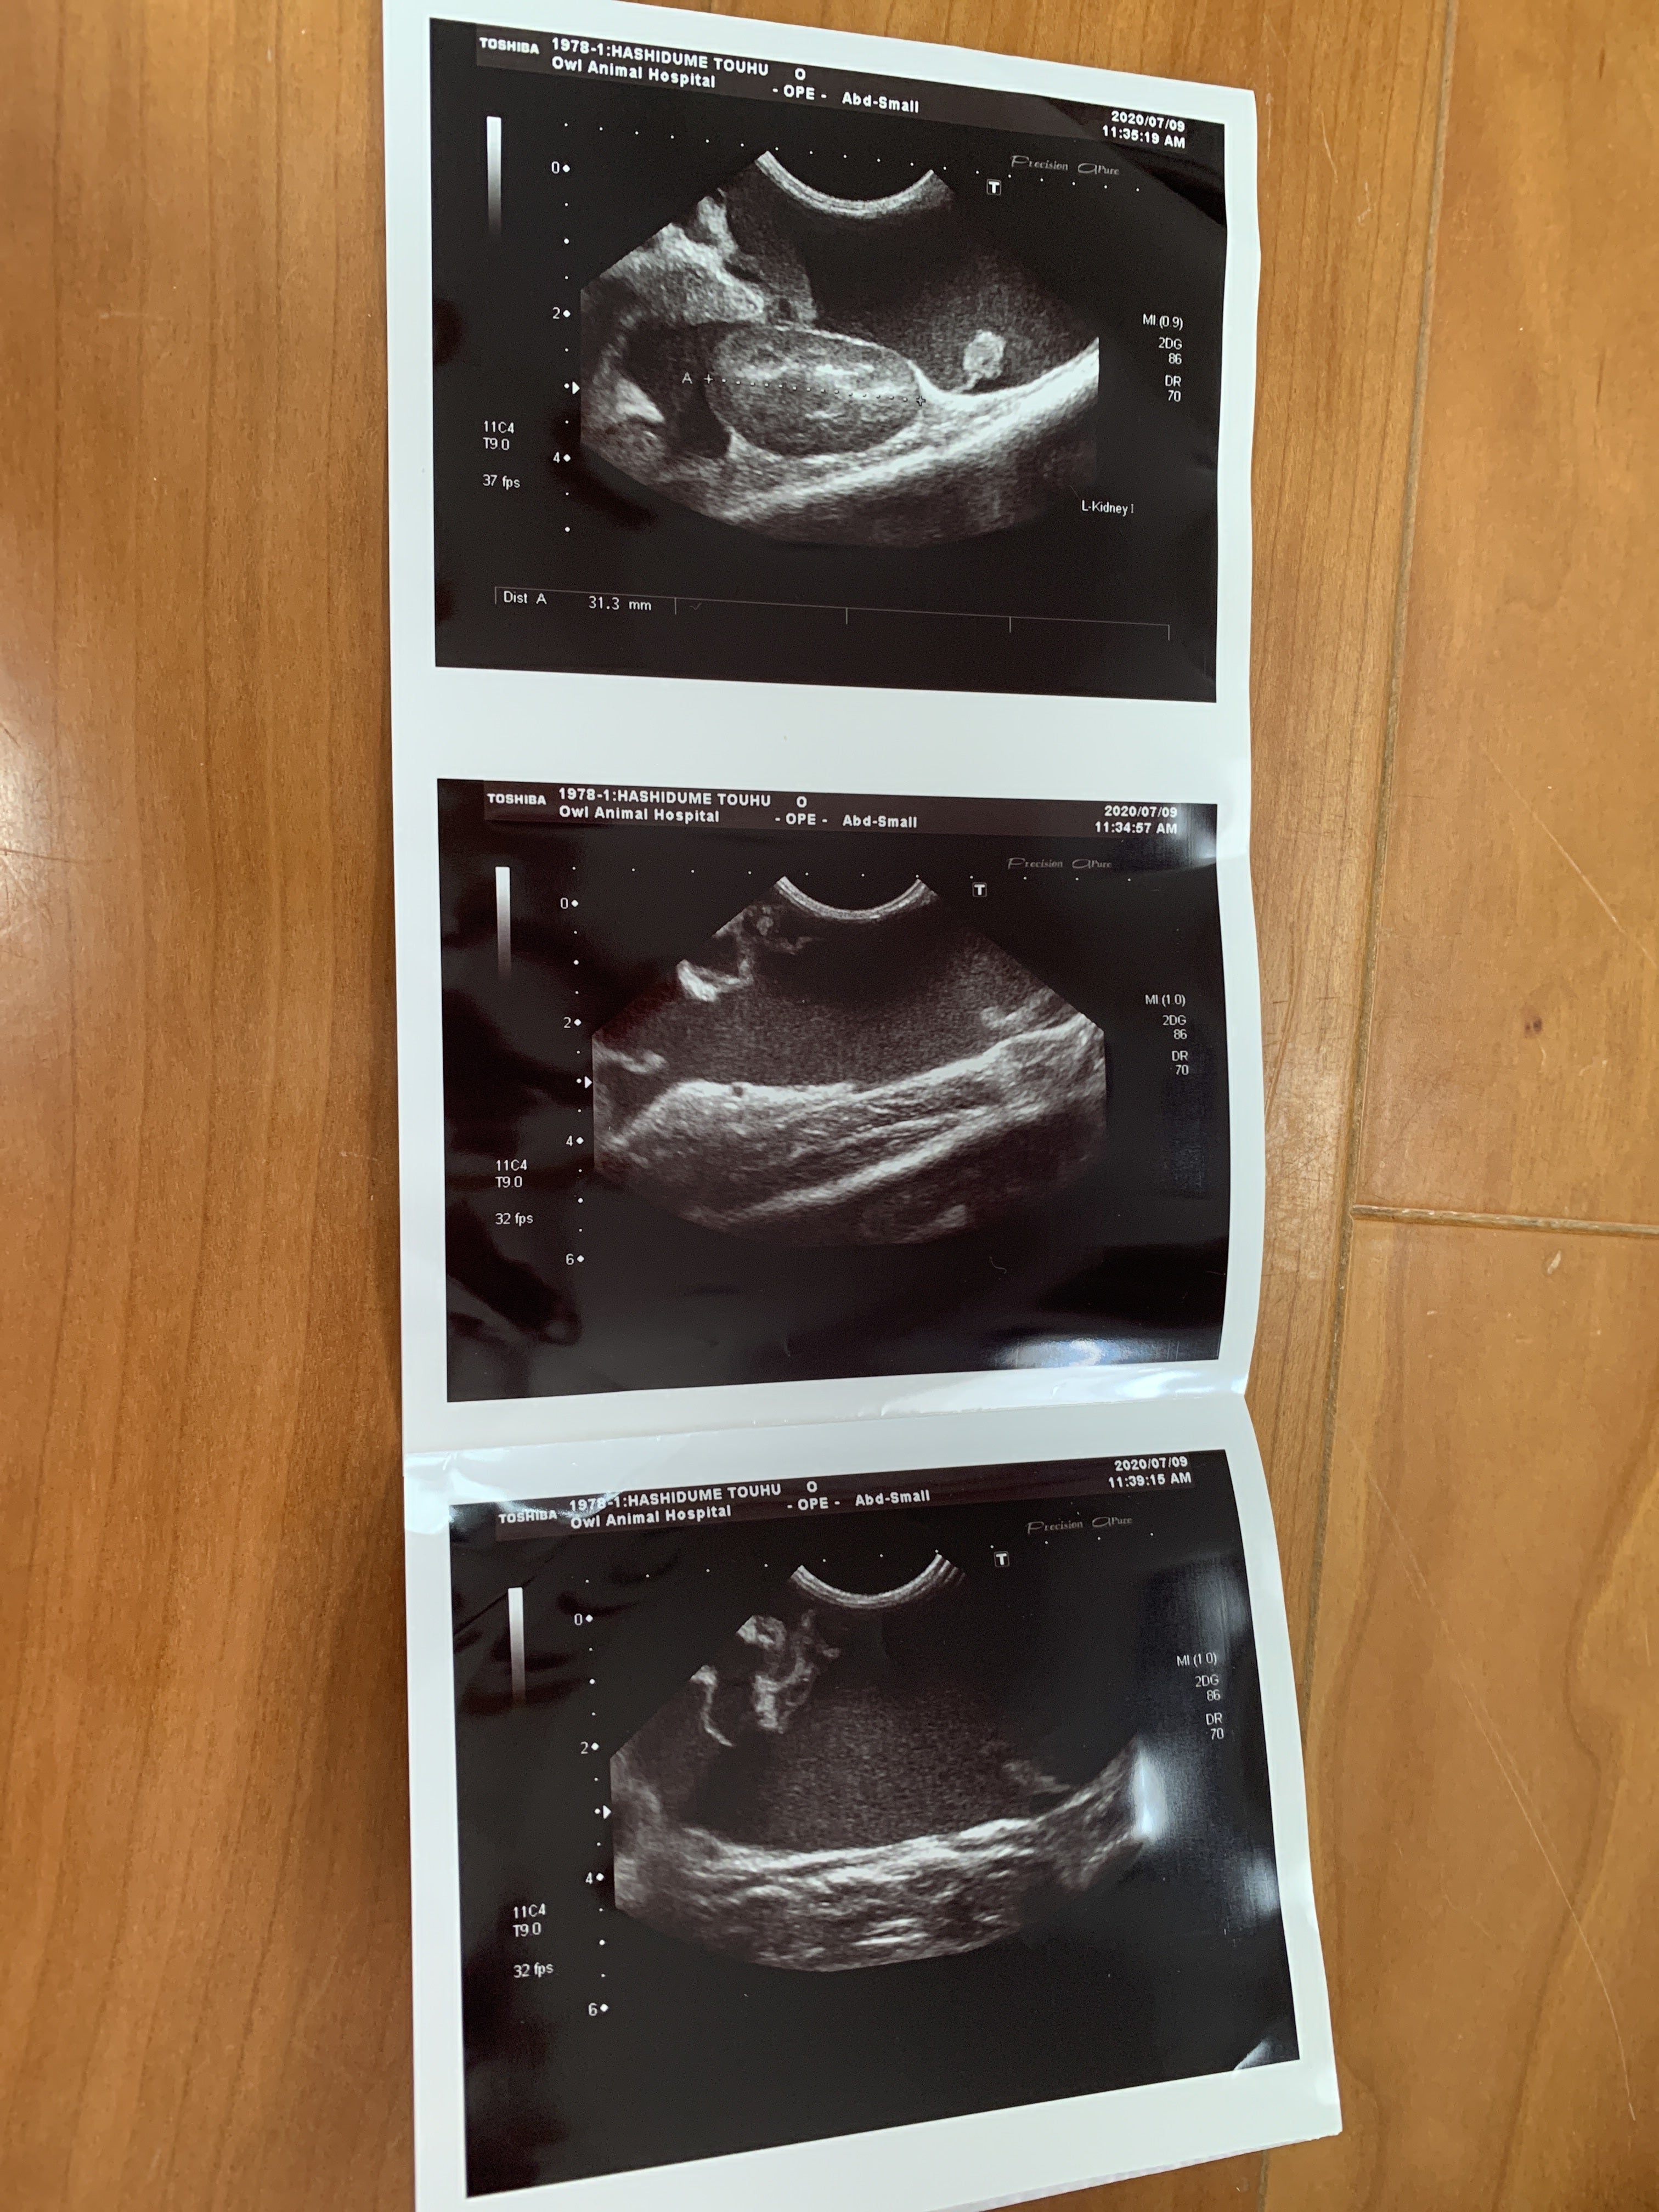

7月9日 朝から病院に連れて行きました。血液検査とエコーの結果

ここで初めて猫伝染性腹膜炎かも知れないと言われました。少しお腹が膨らんでいるのは便秘ではなく腹水でした。私は初めてその病名を聞きました。先生が言うには、このFIP と言う病気は進行が早く数日〜2か月で亡くなる怖い怖い病気ですとの事でした。その後の先生の話を涙が流れるのを必死にこらえて聞いていました。

とうふちゃんの場合 腹水があるので、腹水を外部の検査に出し結果が出るまで5日間くらいかかりますが、検査結果が出てから、また考えていきましょう ただ、その病気だと助かる見込みはないです との事でした。周りに誰も居ない帰りの車では大人げないですが、わんわん泣いてしまいました。とうふと私の帰りを待っていた息子に病院での事を伝えると息子もポロポロ涙を流してとうふを優しく撫でていました。